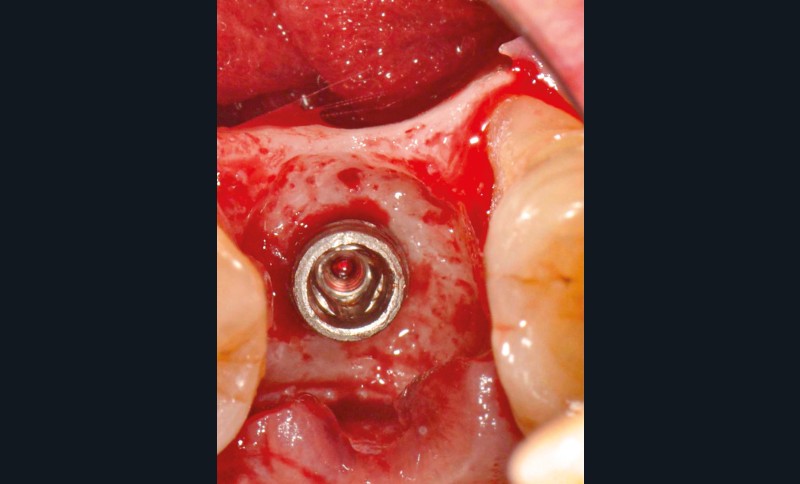

L’implant

- Posé en 2019 par son dentiste

- Couronne d’usage transvissée

- Péri-implantite diagnostiquée en 2020